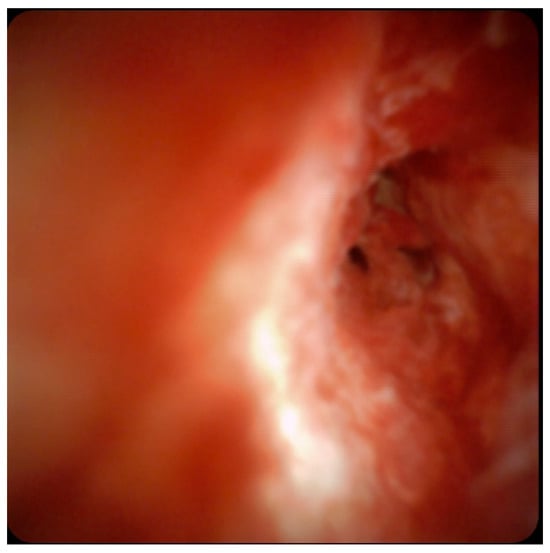

3.4. Cholangioscopy

- Robles-Medranda, C.; Valero, M.; Soria-Alcivar, M.; Puga-Tejada, M.; Oleas, R.; Ospina-Arboleda, J.; Alvarado-Escobar, H.; Baquerizo-Burgos, J.; Robles-Jara, C.; Pitanga-Lukashok, H.; et al. Reliability and accuracy of a novel classification system using peroral cholangioscopy for the diagnosis of bile duct lesions. Endoscopy 2018, 50, 1059–1070. [Google Scholar] [CrossRef] [PubMed]

- De Oliveira, P.V.A.G.; de Moura, D.T.H.; Ribeiro, I.B.; Bazarbashi, A.N.; Franzini, T.A.P.; dos Santos, M.E.L.; Bernardo, W.M.; de Moura, E.G.H. Efficacy of digital single-operator cholangioscopy in the visual interpretation of indeterminate biliary strictures: A systematic review and meta-analysis. Surg. Endosc. 2020, 34, 3321–3329. [Google Scholar] [CrossRef] [PubMed]

- Badshah, M.B.; Vanar, V.; Kandula, M.; Kalva, N.; Badshah, M.B.; Revenur, V.; Bechtold, M.L.; Forcione, D.G.; Donthireddy, K.; Puli, S.R. Peroral cholangioscopy with cholangioscopy-directed biopsies in the diagnosis of biliary malignancies: A systemic review and meta-analysis. Eur. J. Gastroenterol. Hepatol. 2019, 31, 935–940. [Google Scholar] [CrossRef] [PubMed]